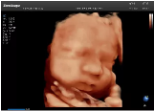

4容積探頭

積探頭是在二維圖像的基礎(chǔ)上,將連續(xù)采集的空間分布位置,經(jīng)過計(jì)算機(jī)重建算法,從而獲得完整的空間形態(tài)。

適用于:胎兒面部、脊柱和肢體等。

優(yōu)勢(shì)特點(diǎn):快速獲取、掃查連續(xù)均勻、解剖結(jié)構(gòu)顯示為容積數(shù)據(jù)、準(zhǔn)確進(jìn)行容積測(cè)量。